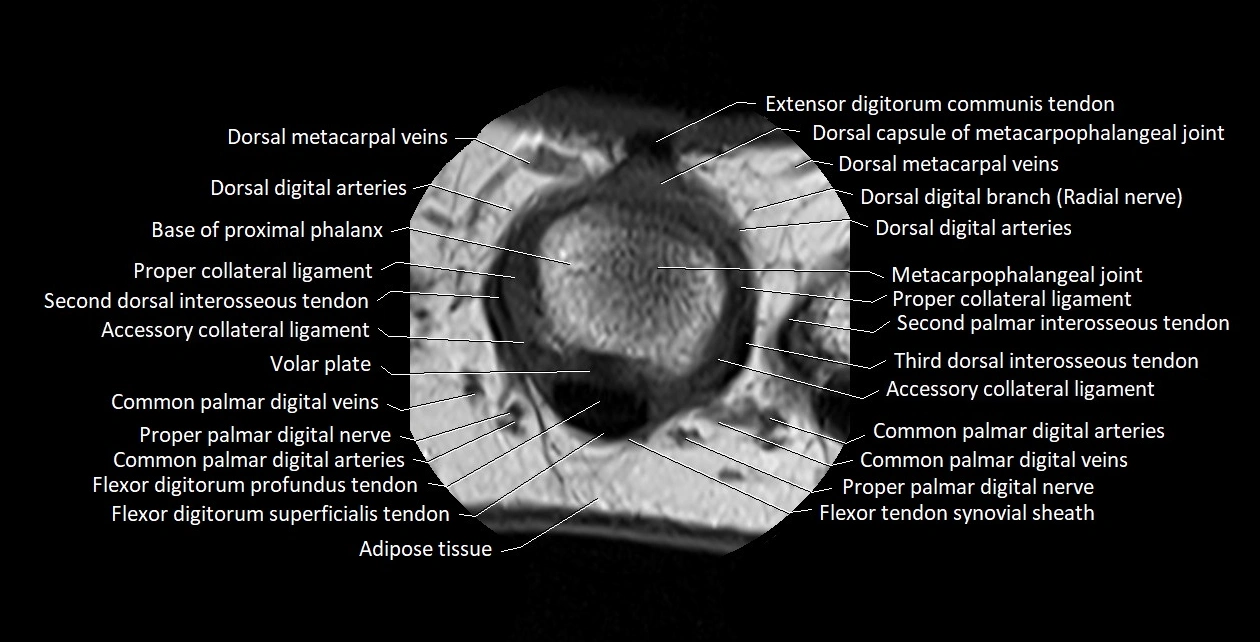

MRI images